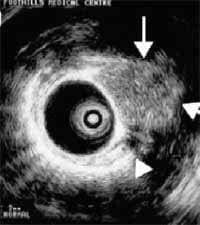

Estos dos últimos procedimientos se pueden realizar de manera más segura con ultrasonido endobronquial, una nueva técnica, que ayuda a delimitar más el compromiso extraluminal de las lesiones (29,30) como se puede observar en la Figuras 1 y 2.

Figura 10. Fibrobroncoscopia con catéter para ultrasonido endobronquial (29).

Figura 11. Catéter de endoscopia intrabronquial, con balón inflado con agua como medio de contraste (29).

Figura 12. Visión ultrasonográfica endobronquial del tumor carcinoide endobronquial señalado por la flechas (29).